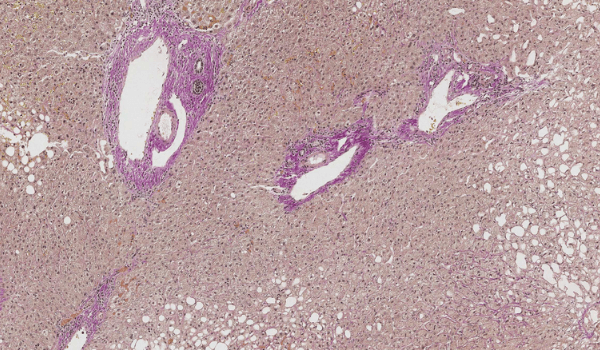

A pathologist studying primary sclerosing cholangitis (PSC) created a deep learning AI model to evaluate novel prognostic biomarkers of the liver disease.

Case study: AI model can improve large droplet fat quantitation in liver pathology

Dr. Maxwell L. Smith from Mayo Clinic built an AI model to accurately estimate large droplet fat in liver sections prior to transplantation.

NAFLD case study: assessing liver histology with AI

This case study describes the use of AI in studying nonalcoholic fatty liver disease (NAFLD) and its capability to segment structures in liver histology.

Case study: AI models aiding chronic cholestasis detection

Developing an automated image analysis tool to assess the amount of K7-positive hepatocytes in any liver biopsy specimen.